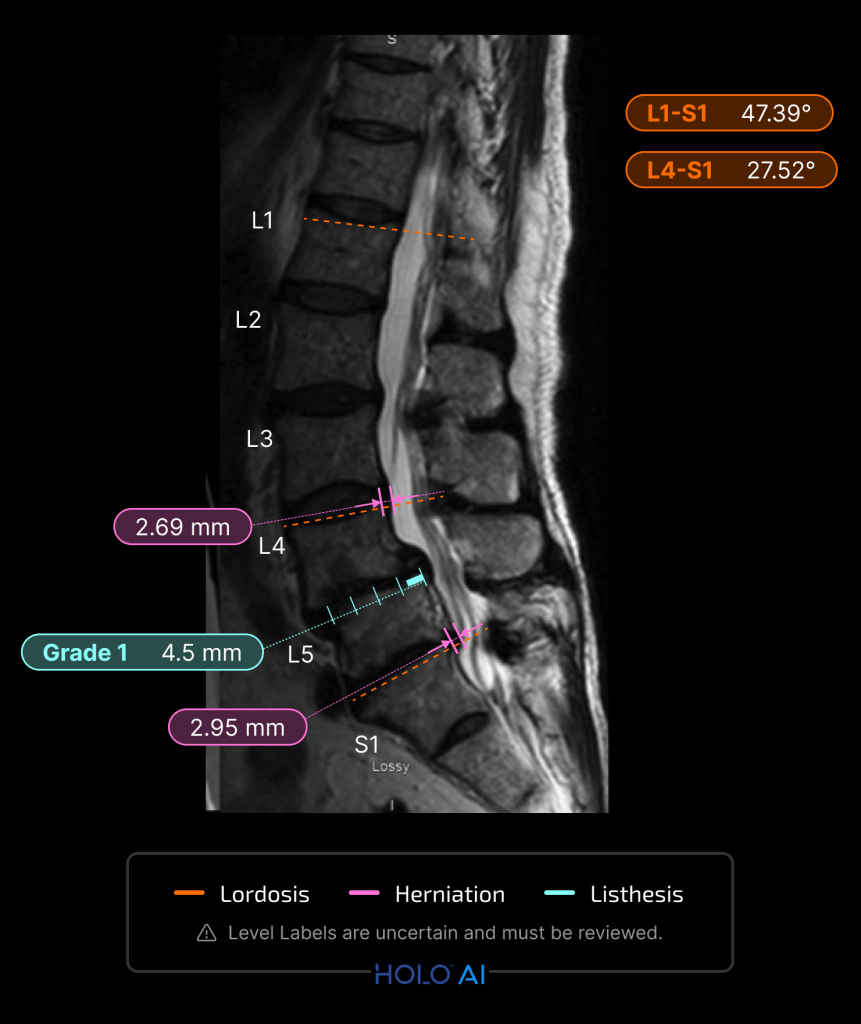

Designing and implementing three new sets of DICOM series (Summary, Sagittal, Axial) enhanced by AI to be viewed alongside original images, optimizing visual appeal and user experience through collaboration with physician consultants and detailed design systems, ultimately bridging the gap between machine learning outputs, customer requirements, and business goals.

I began by delving into various visual possibilities and experimenting with them alongside our physician consultants. Gathering feedback from these sessions, I collaborated with the team to refine and solidify the designs.

Throughout this process, I used my clinical expertise from supporting 1000s of cases and learning physician workflows. For instance, when presenting to the engineering team, I emphasized the technical aspects of the product’s implementation, using detailed schematics and mock-ups to illustrate feasibility and functionality.